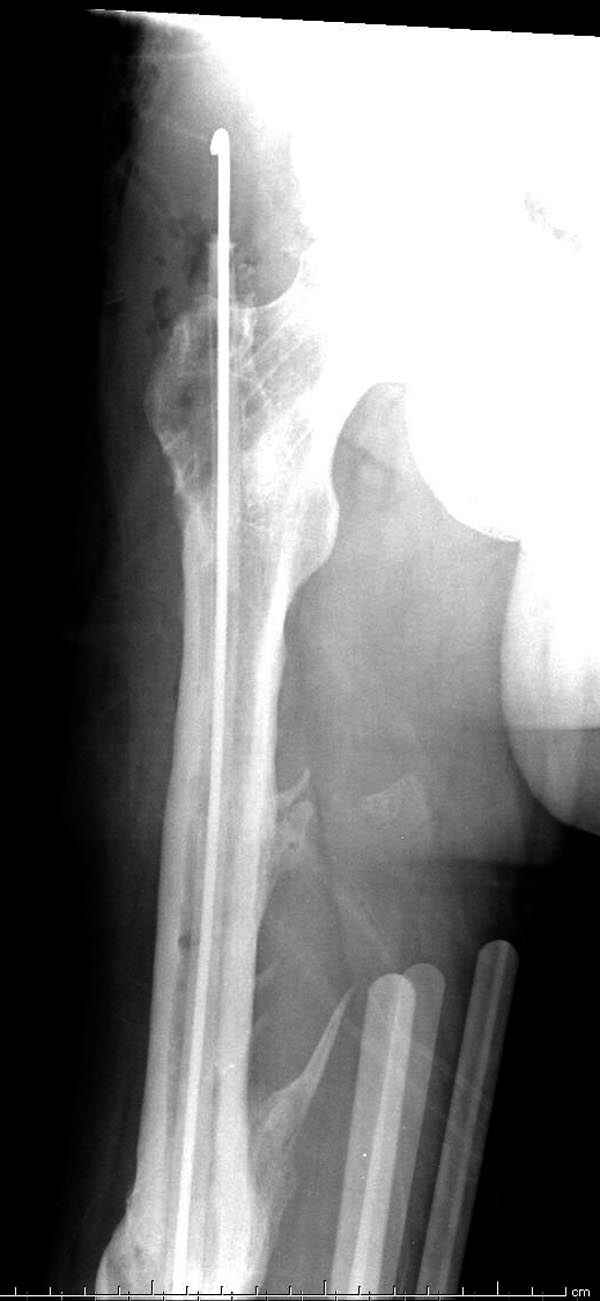

Инфекция канала и стрессовый перелом:

Представляю снимки больного с политравмой: леченного в другом мед.учреждении по поводу открытого перелома бедра, сперва аппаратом наружной фиксации, затем пластиной. Обратился к нам через 8 месяцев после удаления пластины с проблемой несросщего перелома бедренной кости, без клинических проявлении к инфицированию (не все снимки сохранены)

Рутинный интрамедуллярный остеосинтез с расверливанием и с фиксацией реконструктивным трокантерик штифтом (рис №1, №2),

если первые 4 месяца послеоперационного периода проходил без проблем, но на 5 месяце появились боли в дистальном отделе бедра и температура, т.е. симптомы медуллярного инфицирования (рис №3, №4).